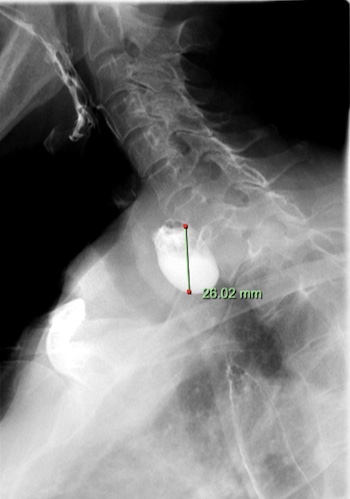

Zenker’s diverticulum (also known as an oesophageal pouch, grey arrow Figure A below) may cause difficulty with swallowing, choking attacks, regurgitation and halitosis (bad breath). Most of these symptoms are due to retention of food debris or liquids within the pouch.

Your doctor will first discuss the risks of the procedure with you and address any questions you may have. You will then meet your anaesthetist who will discuss all aspects of the anaesthetic. Following this you will be taken to the procedure room. You'll then lie on your side, and a needle will be placed in your hand or arm. This is used to administer the anaesthetic. Once you are completely asleep your doctor will pass the endoscope through your mouth and into the oesophagus, stomach and duodenum. A flexible feeding tube will be placed through the mouth and into the stomach (B, black arrow). This is attached to the side of your face using adhesive tape. The muscle ridge that separates the diverticulum from the oesophagus is then incised using endoscopic instruments (C and D) and the incision is closed using an endoscopic clip. The procedure usually takes around 30-45 minutes and you will then be taken to the recovery area.